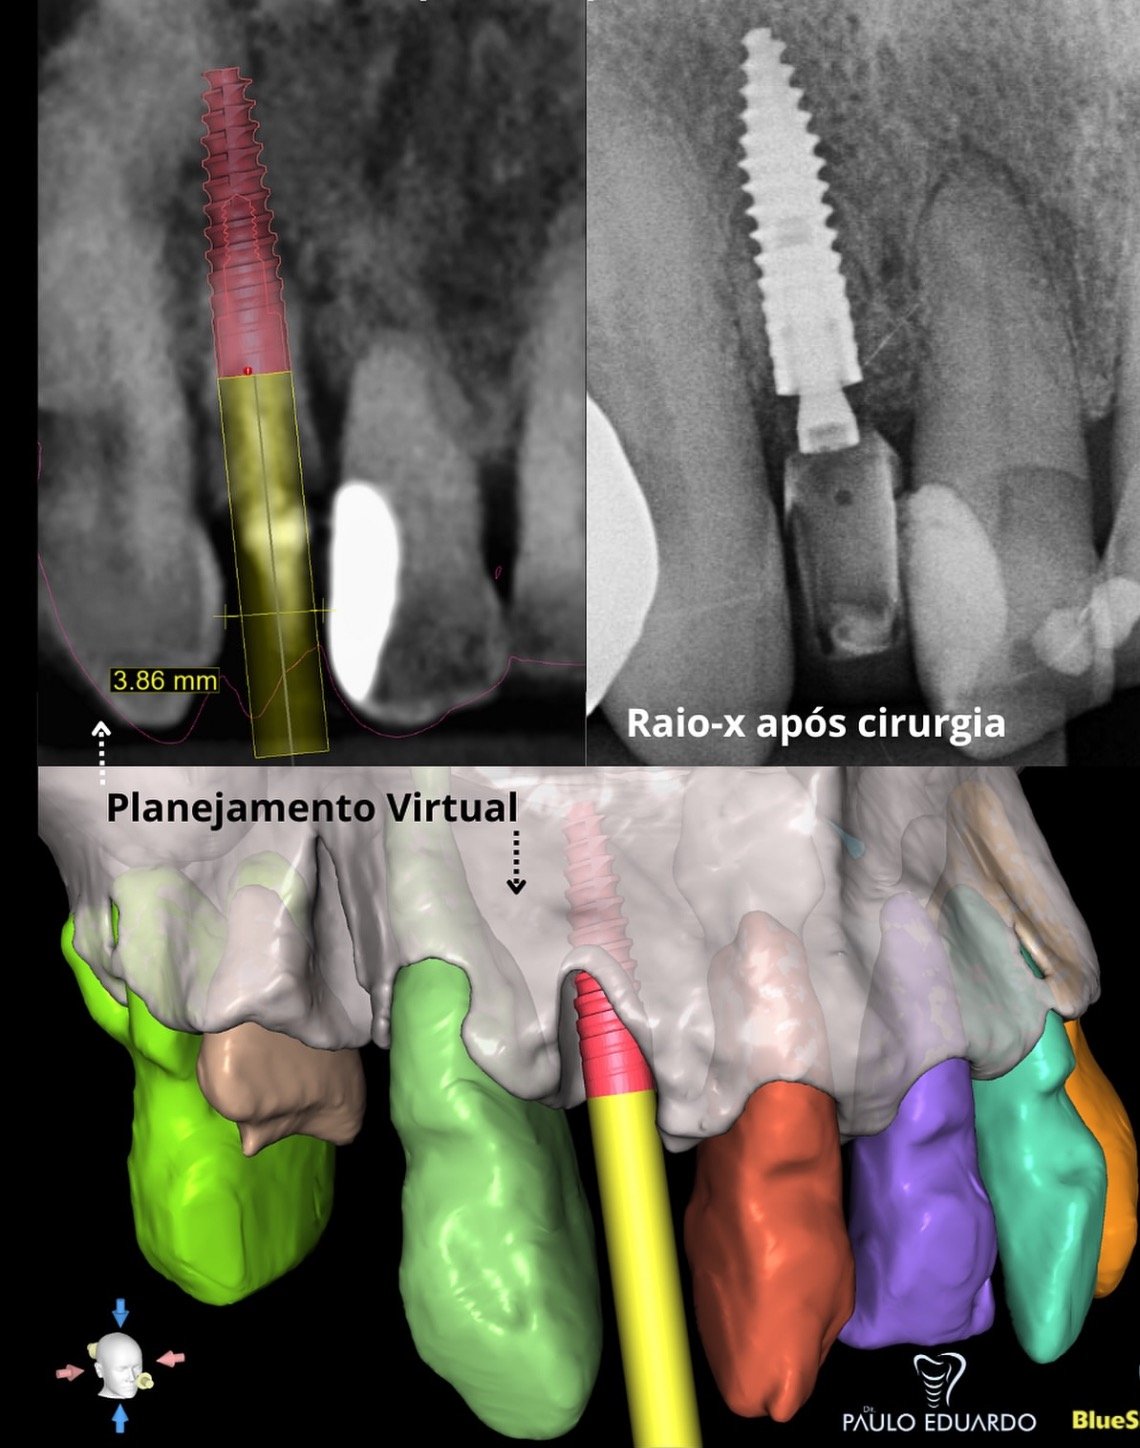

Curso especializado em técnicas de reabilitação com implantes dentários utilizando técnicas atualizadas e avançadas com planejamento digital em softwares específicos.

Treinamento prático para evolução nas técnicas de implantes.